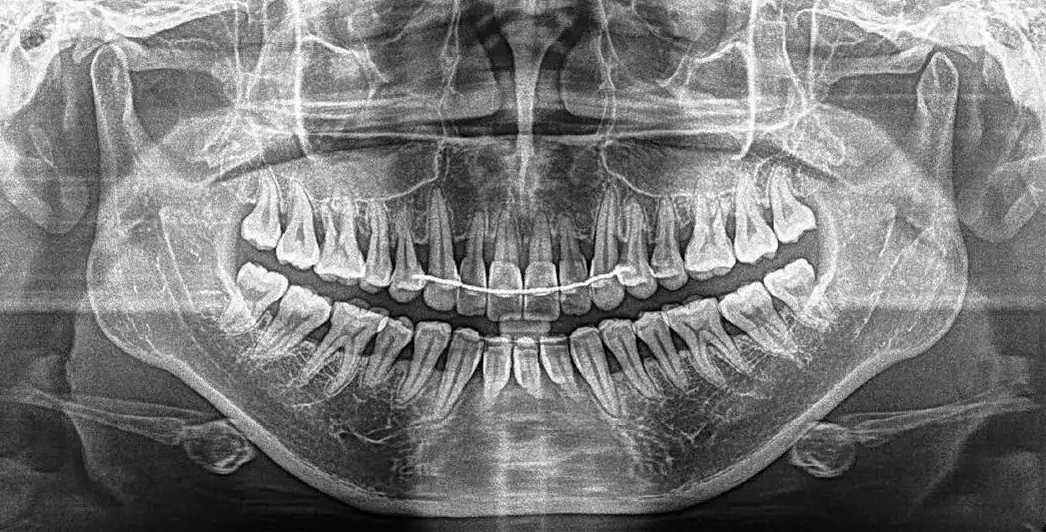

全景片常用于口腔疾病的大范围筛查,例如全口牙齿缺失筛查、颌骨多发病变、颌骨外伤、颌骨发育畸形及牙齿、牙周疾患的诊断。得益于其广泛的成像视野,全景机在正畸领域也能起到数据辅助的作用。

口腔设备有什么一文读懂 | 口腔影像设备大科普,哪种才是最适合你的选择?_https://www.jmylbn.com_新闻资讯_第8张

▲全景片

相较小牙片,全景机成像中牙齿内部的清晰度和细节要略逊一筹,而且由于是曲线体层成像,最终的影像会有较为严重的畸变失真现象,还容易产生重叠的虚影因此,在牙齿种植等对牙齿结构成像清晰度要求非常高的口腔服务领域,很难仅靠全景机制定准确的诊疗方案。